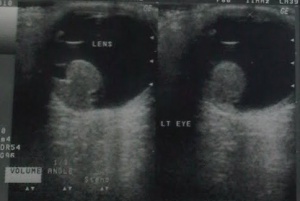

Retained lens material (posterior dislocation of lens fragments)

After posterior capsular rupture with dropped lens material in the vitreous cavity, the USG locates the lens material and gives an idea of the size of the lens fragments. The lens matter appears as a lesion in the vitreous cavity (usually inferiorly) with moderate to high amplitude which moves on ocular movement.